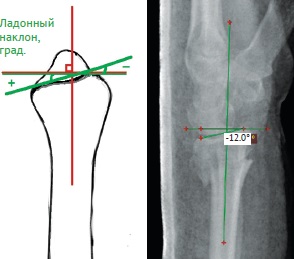

Нами были изучены и проанализированы основные рентгенологические параметры поврежденного сегмента лучевой кости как на предоперационном этапе, так и после операции (рис. 1, 2, 3).

Рис. 1. Оценка высоты и инклинации лучевой кости на предоперационном этапе: уменьшение нормальных величин обоих параметров

Fig. 1. Assessment of the radial height and radial inclination at pre-operative period: it is noted the reduction of the normal value of both parameters

Рис. 2. Оценка ладонного наклона суставной фасетки лучевой кости на предоперационном этапе: отмечается отрицательный ладонный наклон

Fig. 2. Volar tilt assessment at pre-operative period: a negative volar tilt of distal radius